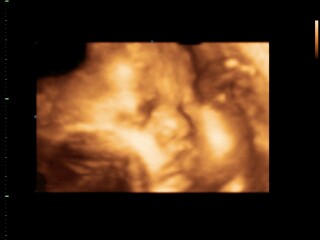

แม่ๆบ้านใหนคลอดเดือนมีนาคมเมษายนบ้างค่ะ ขอดูภาพอัตตราซาวหน่อยจ้าว่าโตแค่ใหนแล้ว